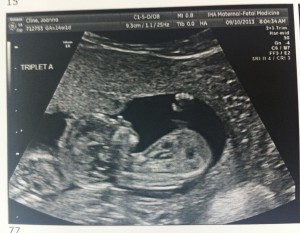

Hello!! I’m 16 weeks today and it was the BIG appointment where we learned the sex of the fetuses!!

A is 170 grams, B is 175 grams and C is 178 grams so they’re all measuring well. Grow, grow, grow!

Our next appointment is at 18 weeks for big anatomy ultrasound. Can’t wait!